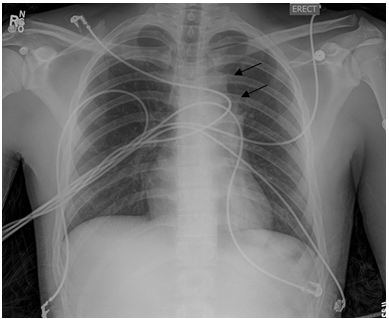

A 20 year old Caucasian man with no significant past medical history presented to his primary care physician for chest discomfort and cough. Two months prior to presentation, he reported having an unremarkable viral syndrome which resolved with no medical intervention. His primary care physician prescribed a short course of antibiotics for empiric treatment of pneumonia with some initial improvement in symptoms. His chest discomfort returned and he developed progressive dyspnea on exertion which led to a chest radiograph (CXR) (Figure 1).

Figure 1. Posterior-anterior chest x-ray (CXR) demonstrating left-sided mediastinal mass (arrows).

An abnormality was noted in the left mediastinum which prompted his physician to order a computed tomography (CT) of the chest and to refer him to a pulmonary specialist. This CT scan (Figures 2 and 3) revealed a rounded, well-demarcated mass in the superoanterior mediastinal compartment. The largest diameter measured 6.8 x 4.8cm.